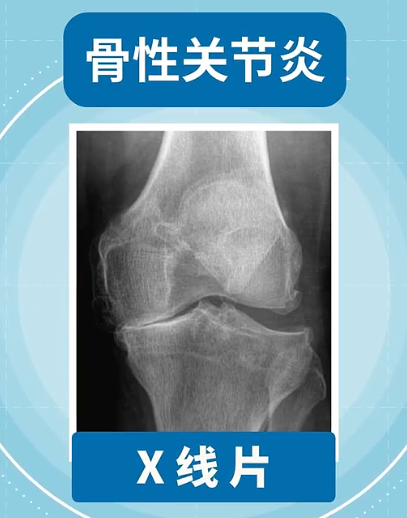

骨性关节炎主要通过X线片来明确诊断,表现为:关节间隙变窄、软骨下骨硬化和(或)囊性变、关节边缘骨赘形成等。